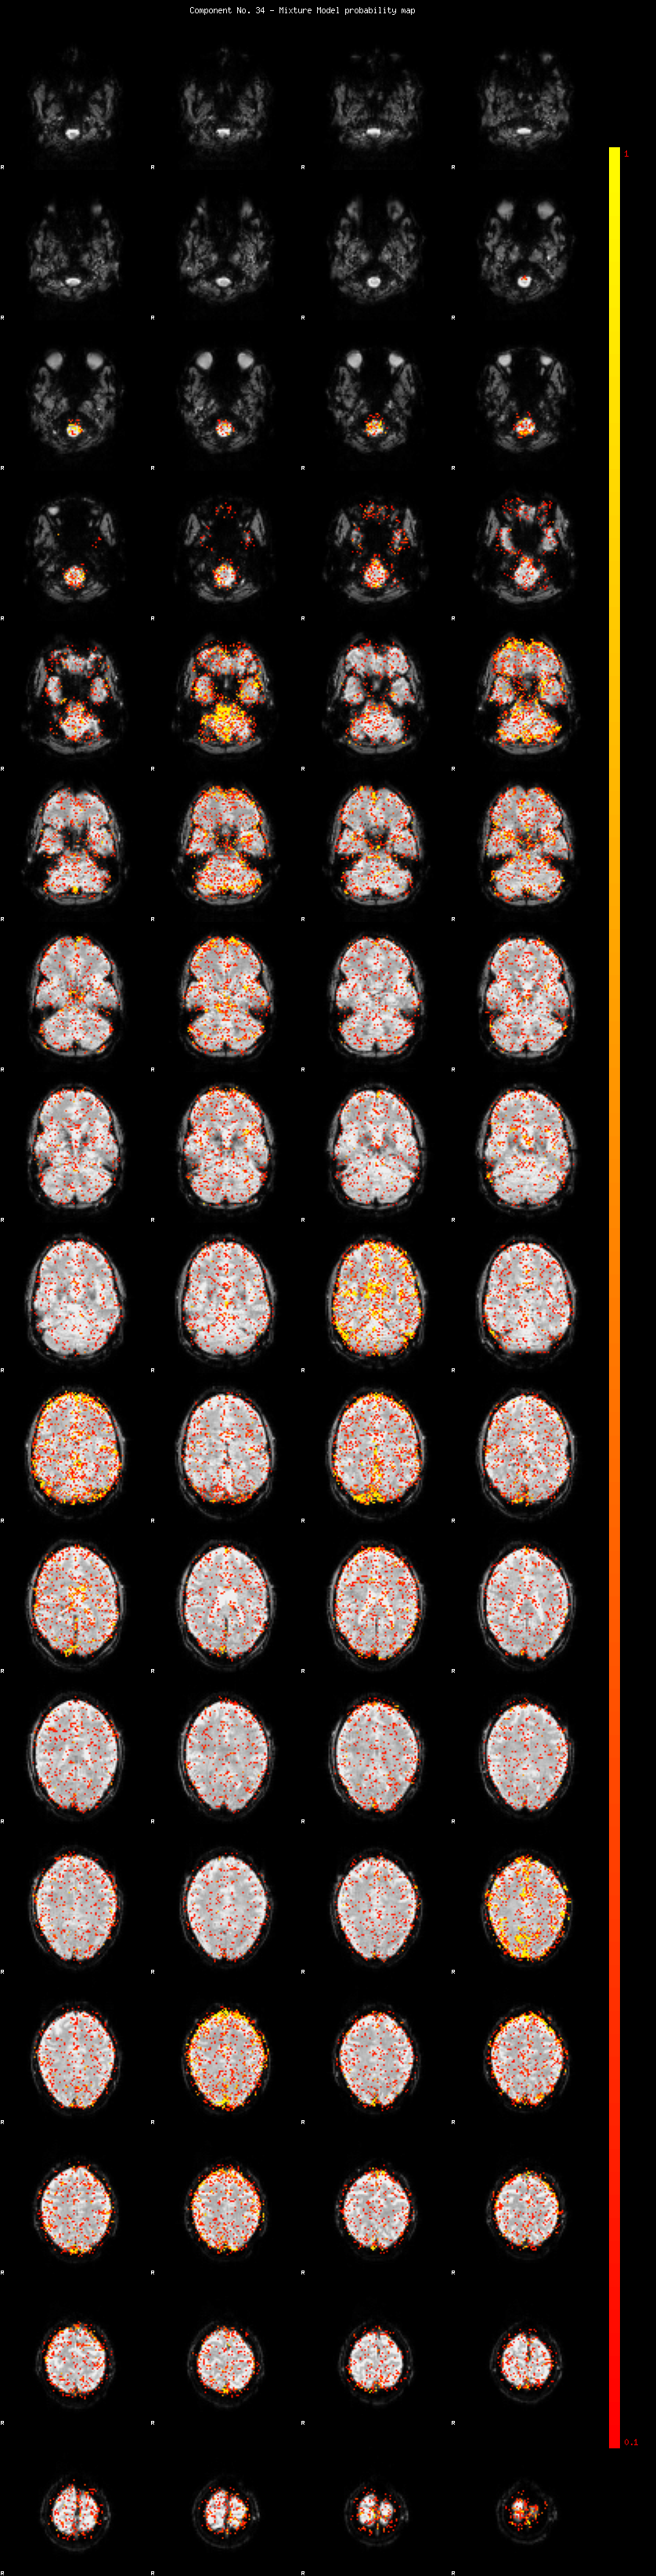

IC_34 Mixture Model fit

Means : 0.000000 2.491848 -2.335351

Vars : 1.000000 2.012908 1.566577

Prop. : 0.927005 0.041760 0.031235